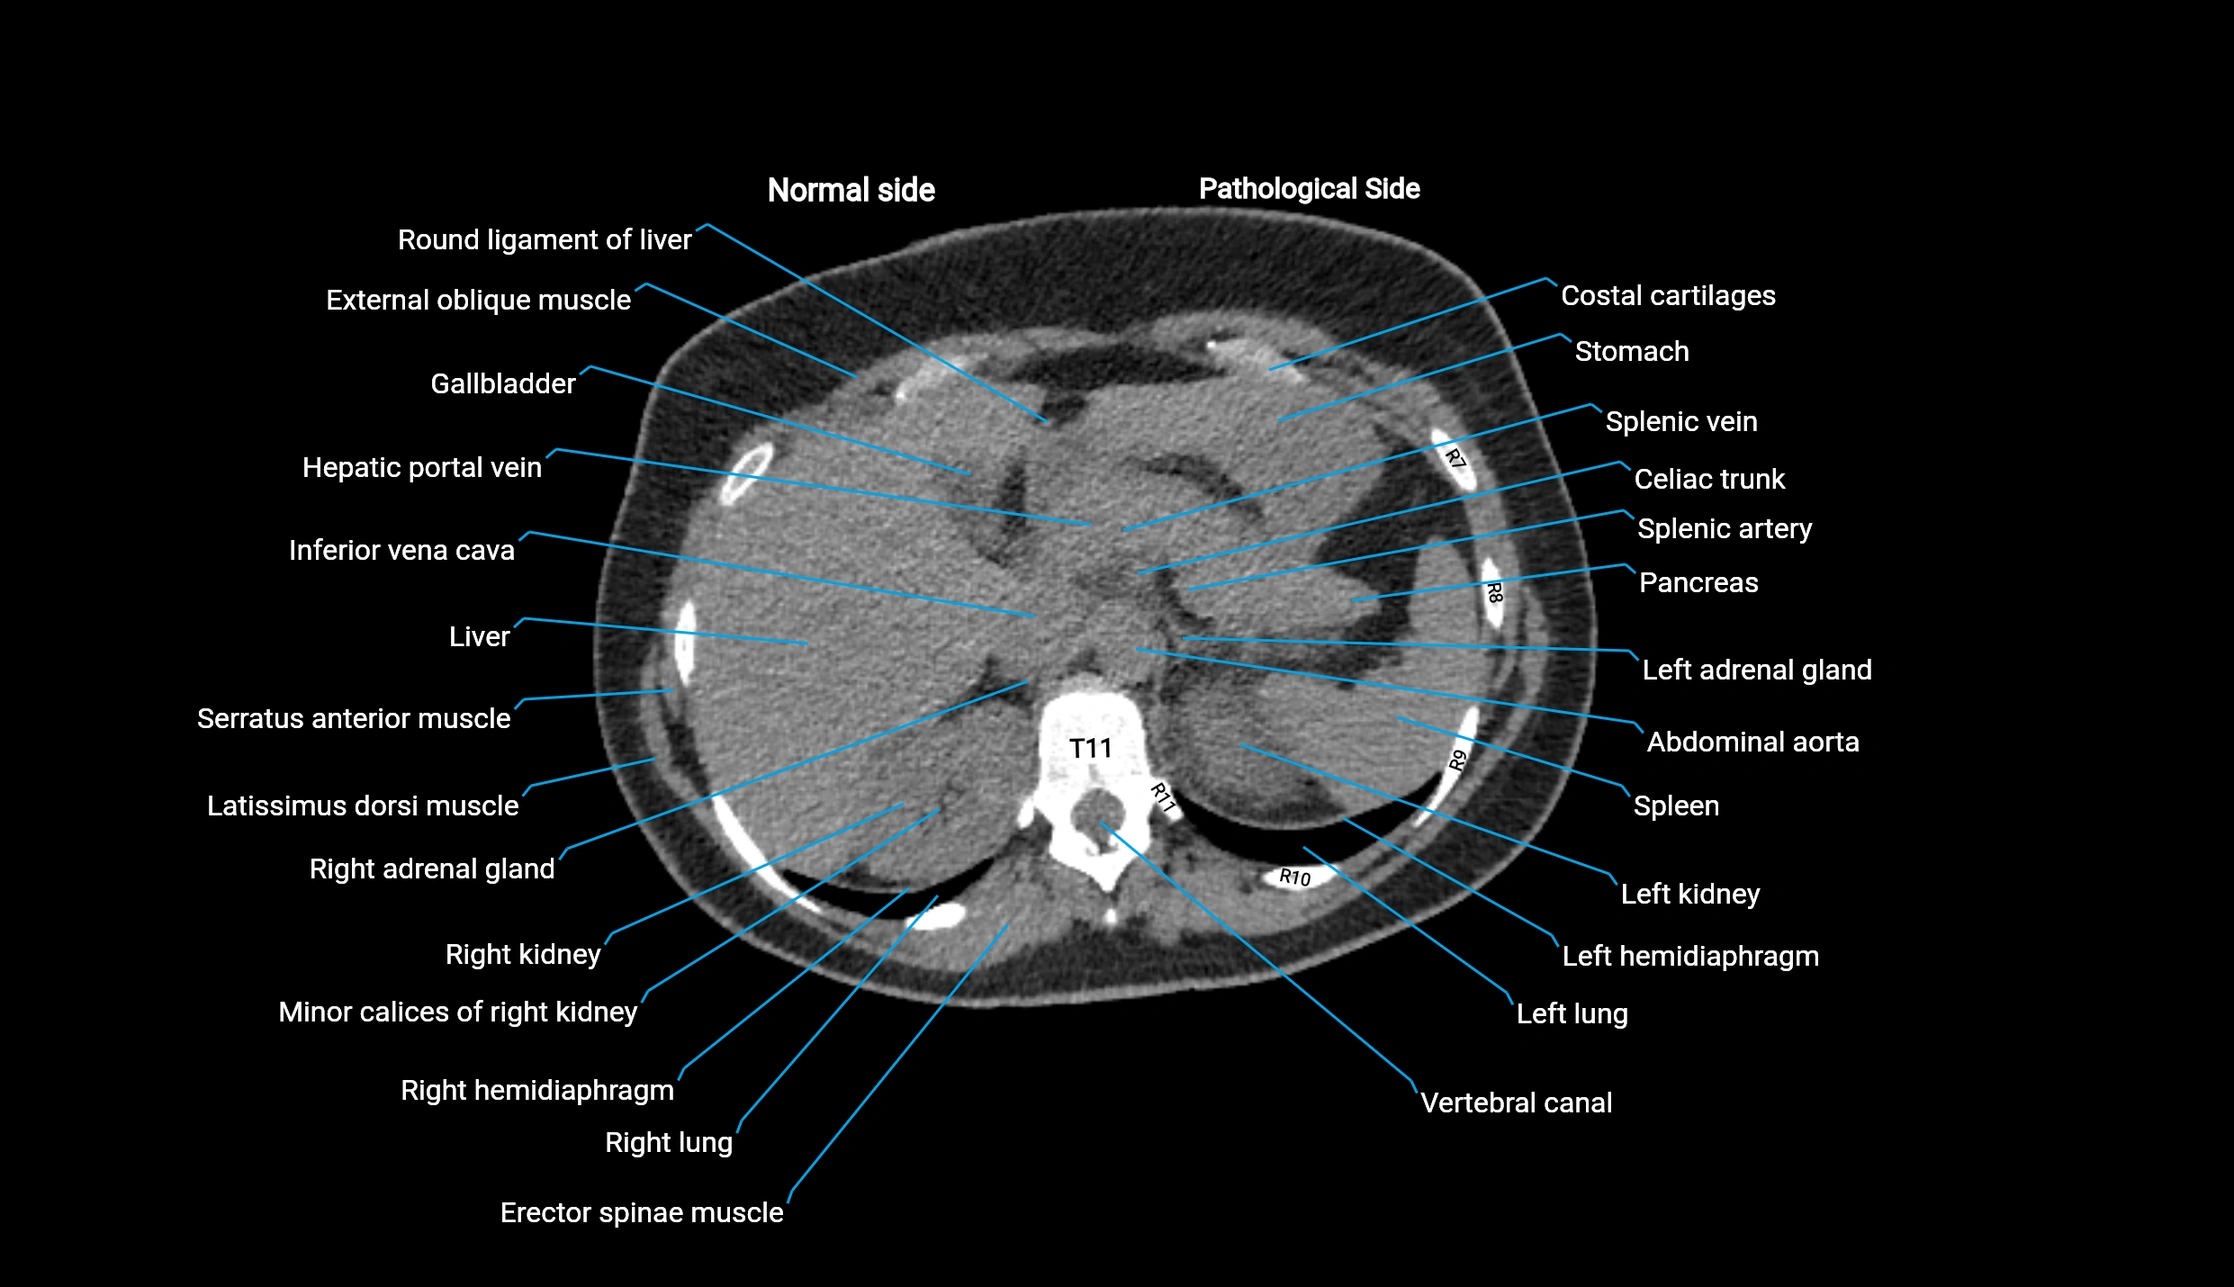

Post-Contrast CT (Contrast-Enhanced CT):

• Portal venous phase:

• Anterior right portal branch enhances intensely and homogeneously

• Clearly separates from posterior branch

• Branching pattern to segments V and VIII sharply defined

• Arterial phase:

• Slight enhancement but less conspicuous than in portal phase

• Coronal and sagittal reconstructions:

• Optimal visualization of segmental bifurcation

• Used for preoperative liver mapping

• CT liver segmentation:

• RAPV acts as the principal boundary landmark for dividing anterior vs. posterior right hepatic segments